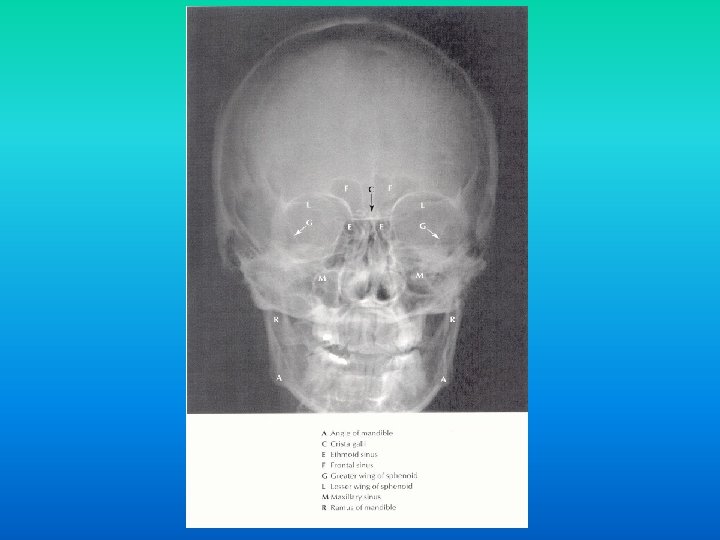

Tehnici de explorare radioimagistica n in functie de bazele fizice sunt: n tehnici ce utilizeaza razele X: n n radiografii, mielografii, CT tehnici imagistice ce utilizeaza alte modalitati de obiectivare a structurilor anatomice: n ecografia, IRM